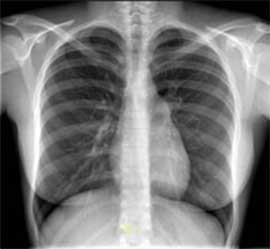

a sombra no pulmão

a crescer e a recolher